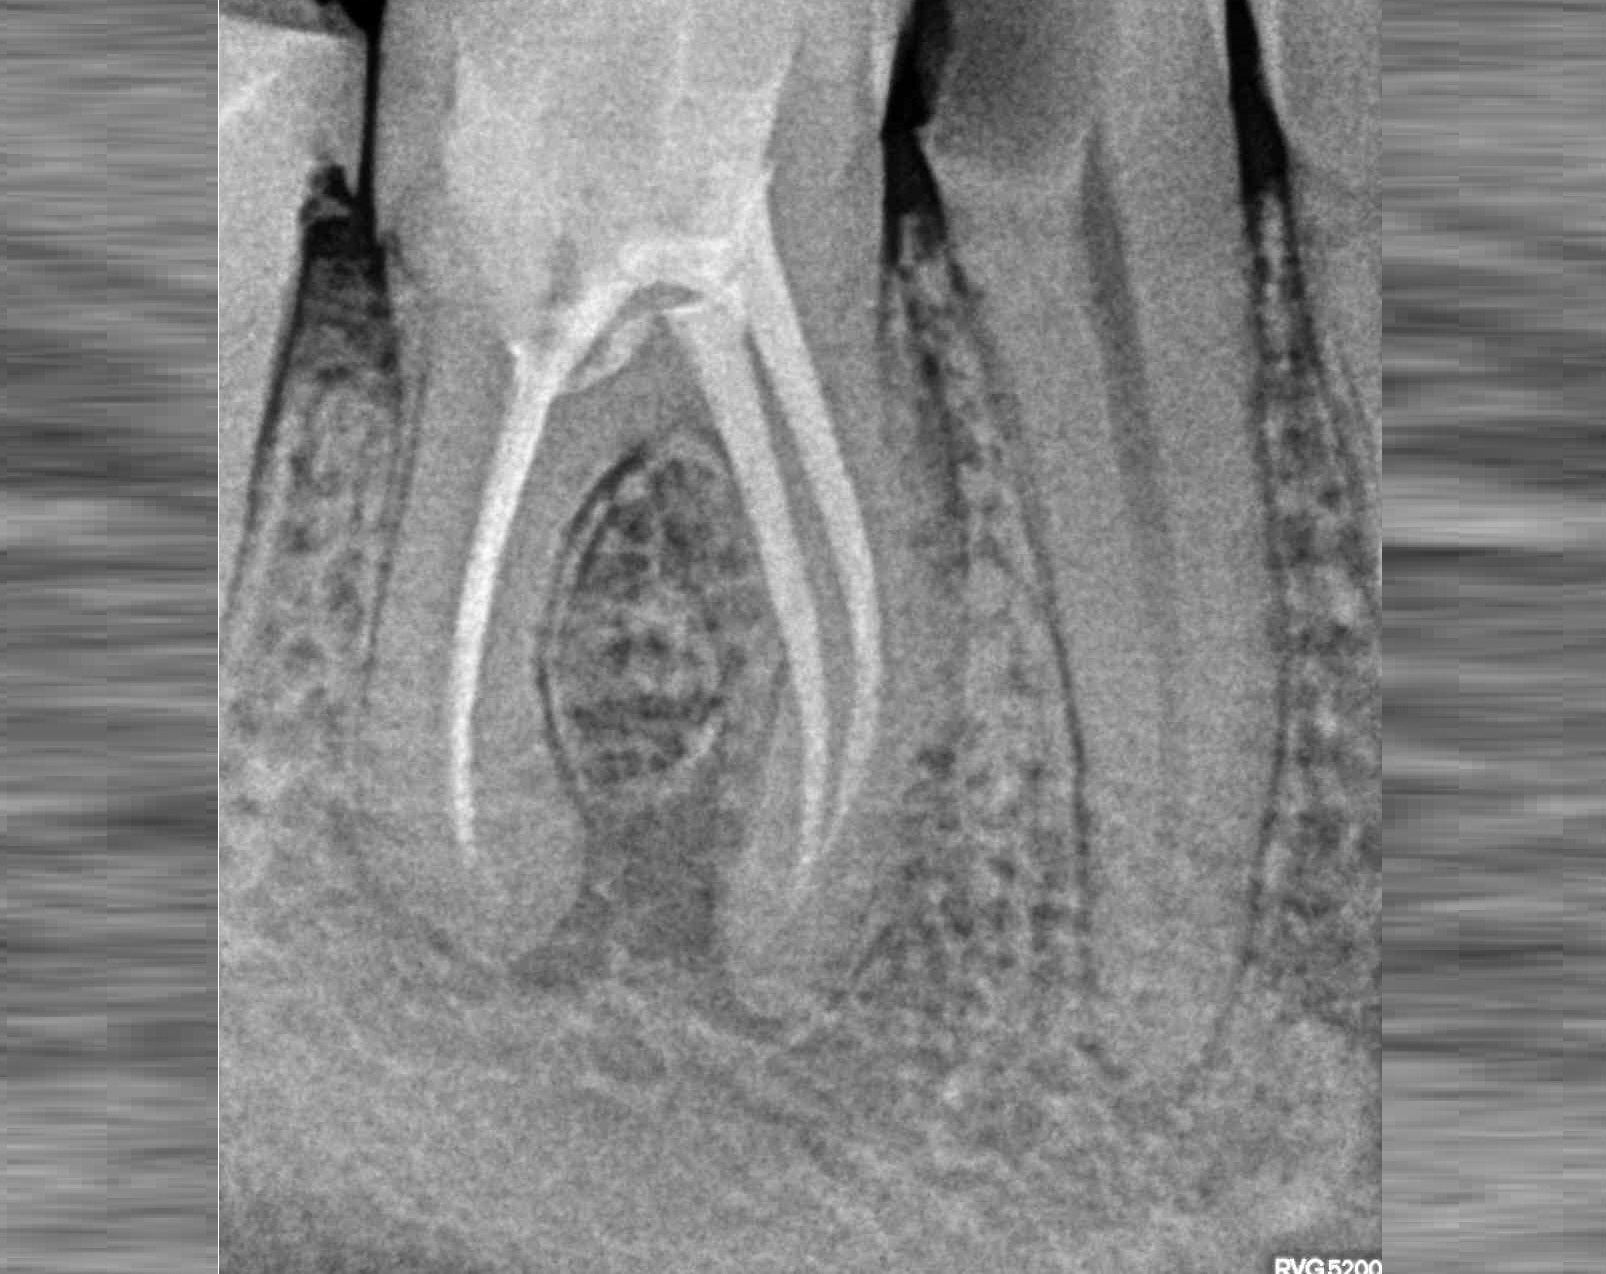

Проблема

Пациент обратился в клинику с постоянными ноющими болями усиливающимися при накусывании.

Решение

В нескольких клиниках было предложено удаление данного зуба. В нашей клинике такие зубы лечат. Пациенту было проведено эндодонтическое лечение данного зуба. Результат положительный, идет восстановление костной ткани.